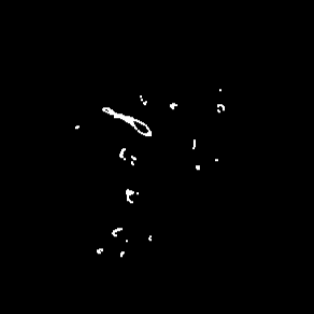

Manually segmenting the hepatic vessels from Computer Tomography (CT) is far more expertise-demanding and laborious than other structures due to the low-contrast and complex morphology of vessels, resulting in the extreme lack of high-quality labeled data. Without sufficient high-quality annotations, the usual data-driven learning-based approaches struggle with deficient training. On the other hand, directly introducing additional data with low-quality annotations may confuse the network, leading to undesirable performance degradation. To address this issue, we propose a novel mean-teacher-assisted confident learning framework to robustly exploit the noisy labeled data for the challenging hepatic vessel segmentation task. Specifically, with the adapted confident learning assisted by a third party, i.e., the weight-averaged teacher model, the noisy labels in the additional low-quality dataset can be transformed from "encumbrance" to "treasure" via progressive pixel-wise soft-correction, thus providing productive guidance. Extensive experiments using two public datasets demonstrate the superiority of the proposed framework as well as the effectiveness of each component.